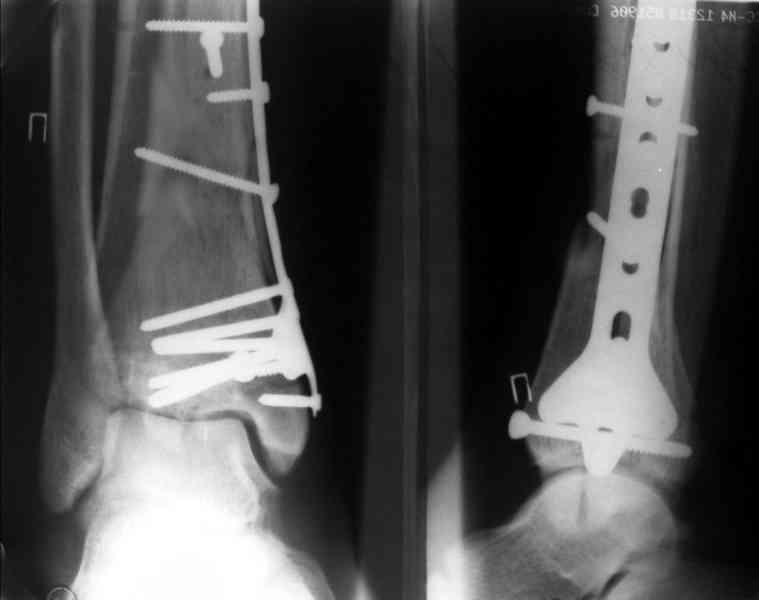

Дрягин В. 03 Январь 2007, 19:11

Посмотрим вроде прошло если понравится напишите расскажу как это сделать.По принципам АО кстати при поступлении сначала восстанавливают длину малоберцовой кости фиксируют пластиной 1/3 трубки потом накладывают аппарат наружной фиксации и через 7-10 дней открыто восстанавливают большеберцовую кость.С уважением Дрягин

На рентгенограммах типичный перелом пилона по типу С-3. есть опыт до 100 открытых опреаций у нас в клинике. 20 примерно в год. Принцип один -все внутрисуставные переломы нуждаются в открытой репозиции и внутренней стабильной фиксации. При поступлении КТ не надо, так как получается только нагромождение костей. Истинной картины нет. Главное восстановить длину малоберцовой кости - это ключ к успеху. При поступлении меньше всего надо думать о сосудистых расстройствах, т.к. сама операция и репозиция даже сначала частичная даёт улучшение сосудитых нарушений. Причём очень быстро. Операция в 2этапа. При поступлении доступ позади наружной лодыжки, причём обязательно. После этого репозиция малоберцовой кости и фиксация пластиной 1/3 трубки под винт 3,5. Дренаж и любой аппарат наружной фиксации. Затем после спадения отёка на 5-7-10 день аппрат снимается и дугообразный разрез спереди от медиальной лодыжки 10-12 см. Главной чтобы расстояние между 1 и вторым разрезом было не меньше 7-8 см. Тогда не будет некрозов лоскутов. Таранная кость используется как матрица на неё укладываются отломки и фиксируются пицами. Ренг-контроль. Отломки лежат все отдельно, но ничего не высыпется. При переломах С-3 всегда нужна костная пластика (из крыла). Фиксация пластиной лист клевера простой или LCP. Гипс не нужен. Дренаж до 48 часов. Операция длится 3-4 часа обязательно без жгута. Посылаю примерно такой же случай.

Ещё есть одна проблема когда есть перелом малоберцовой кость, то всё ясно. А когда малоберцовая кость не повреждена, то сразу накладывается аппрат наружной фиксации при поступлении, чтобы как бы перерастянуть отломки и главное убрать вальгусное или варусное смещение, а потом на 5-7 день открыто большеберцовая кость восстанавливается и фиксируется пластиной. С уважением Дрягин